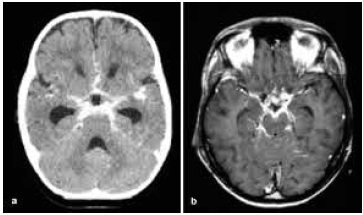

Homem de 52 anos, com histórico de hipertensão arterial sistêmica não aderente ao tratamento, apresenta-se no pronto-socorro com cefaleia súbita e intensa, acompanhada por vômitos e rápida deterioração do nível de consciência.

A tomografia computadorizada (TC) encontra-se a seguir.

Com base nos protocolos atuais para manejo avançado do acidente vascular cerebral hemorrágico (AVCH), das opções apresentadas, assinale a alternativa que melhor reflete a conduta terapêutica inicial mais adequada.